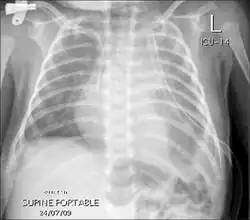

Chest X-rays can detect a chylothorax. It appears as a dense, homogeneous area that obscures the costophrenic and cardiophrenic angles. Ultrasounds can also detect a chylothorax, which appears as an echoic region that is isodense with no septation or loculation. However, neither a normal chest x-ray nor an ultrasound can differentiate a chylothorax from any other type of pleural effusion.[5]